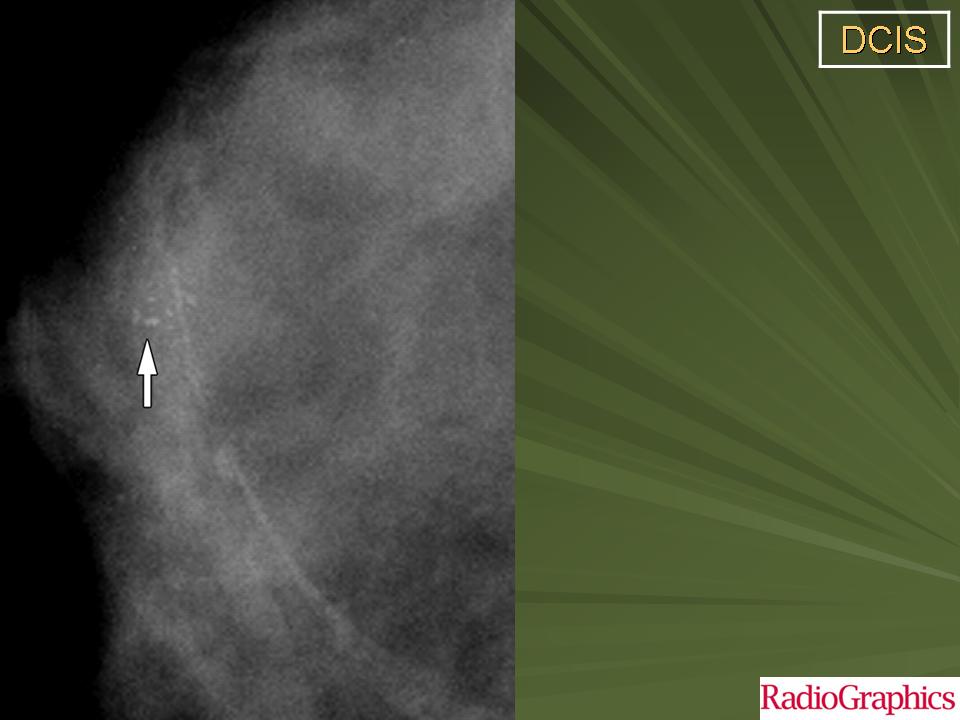

Обычно, ПКИС никак не проявляется и не выявляется при физикальном исследовании. Однако у небольшого числа женщин может отмечаться опухолевидное образование либо какие-то выделения из соска. Чаще всего протоковая карцинома выявляется на маммографии. Дело в том, что «старые» раковые клетки отмирая, не успевают полностью утилизироваться. В результате этого эта область пропитывается солями кальция (так называемое обызвествление) – образуются микрокальцинаты. Эти микрокальцинаты как раз и выявляются на маммограмме. В случае если полученные результаты маммографии врач считает подозрительными на рак, проводится следующий этап диагностики – биопсия.

Часто на маммограммах в области опухоли выявляются микрокальцинаты, что связано с том, что в опухоли происходит омертвление ее клеток (некроз), которые в последствие пропитываются солями кальция. Опухоль при инвазивной карциноме может быть различных размеров, и у клеток может быть различное время деления, так что некоторые клетки растут быстрее других.